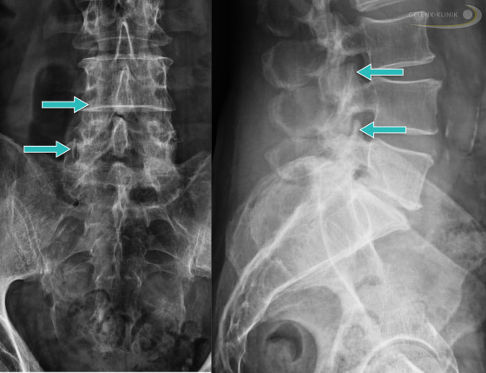

Der Arzt prüft die Beweglichkeit und Sensibilität der Wirbelsäule und testet, wann die Schmerzen im Rücken auftreten. Außerdem ist die genaue Lokalisation der Schmerzen sehr wichtig. Zusätzlich wird ein Röntgenbild, ein CT (Computertomographie) oder eine MRT (Magnetresonanztomographie) angefertigt. Anhand dieser Bildgebungen erkennt der Rückenspezialist knöcherne Veränderungen an den Wirbelgelenken oder andere Wirbelsäulenschäden wie Bandscheibenvorfälle. Um festzustellen, ob die Schmerzen wirklich von den Facettengelenken und nicht von einer anderen Struktur wie den Bandscheiben oder den Nervenwurzeln ausgehen, kann es sinnvoll sein, die betroffenen Gelenke zu betäuben. Dafür injiziert der Arzt unter Röntgenkontrolle ein Schmerzmittel (Wirbelsäuleninfiltration). Die Arthrose ist dann nachgewiesen, wenn der Patient nach der Injektion eine Zeit lang schmerzfrei ist.